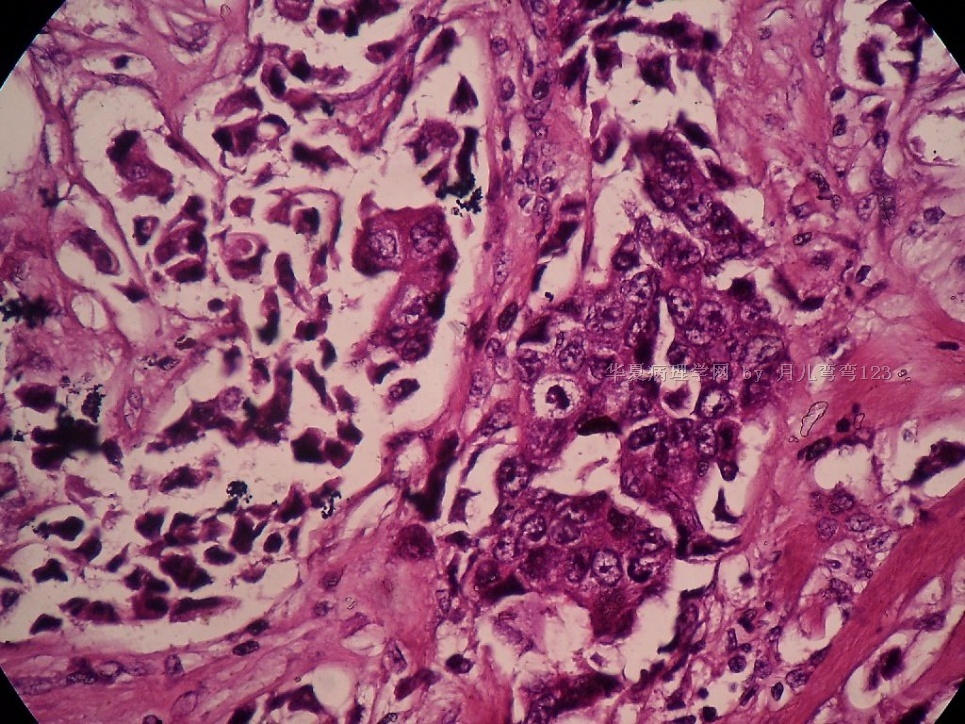

姓    名: ××× 性别:  女 年龄:  45

标本名称:  左侧近乳晕处肿物

简要病史:  患者描述有疼痛

肉眼检查:  肿物一个2.5*2*1厘米,切面灰白质地硬。

• 浸润性导管癌?图1

上皮样细胞,大部分粘附成团成巢,明显浸润。大部分细胞大,核级别高,少数图中见松散的小细胞。未见原位癌。

大细胞考虑浸润性导管癌(3级),小细胞要排除小叶癌。如果有条件请做免疫组化。

Most likely it is INVASIVE DUCTAL CARCINOMA.

DO ER/PR/HER2 STAINS

应该是浸润性导管癌,标本可能有部分自溶现象。